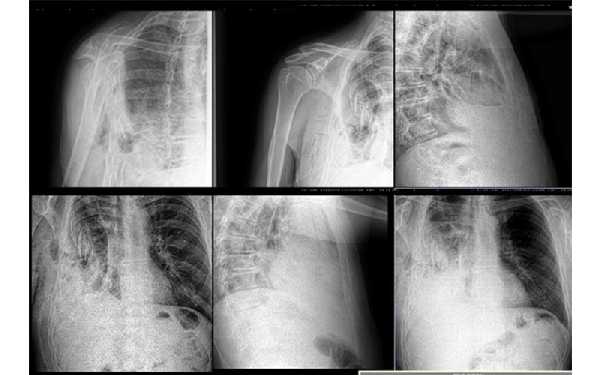

From the first days we started to provide assistance to wounded civilians and the military from different parts of our country. Our work is to diagnose various injuries of the chest, abdomen, skull, pelvis and especially the limbs. We help thoracic, abdominal and facial surgeons, ophthalmologists, and especially orthopaedists in preoperative and postoperative stages of the treatment.

One of our tasks, as radiologists, has been to find foreign bodies in the people’s arms, legs, abdomen and thoracic wall with help of radiography or ultrasound. We also help in finding traumatic injuries to internal organs. Despite the lack of new equipment, we try to help all our patients as much as possible. Psychological support of patients is also important in our work, which I am doing.

Most examinations of the wounded are carried out in the wards due to the severity of the patients' condition, and X-rays are taken with the help of traditional non-digital machines. We are still waiting for the state CT scan in the hospital, we have only private near the hospital. The MRI machine (0.75 T) has been in use for more than 20 years. Among five stationary X-ray machines, only two are digital, and those without remote access to data for control, comparison. Of the eight ward X-ray machines, only one is digital. Our American colleagues presented it to our hospital. In some departments and operating theaters, there is no US equipment and C-arches for controlling operation procedures.